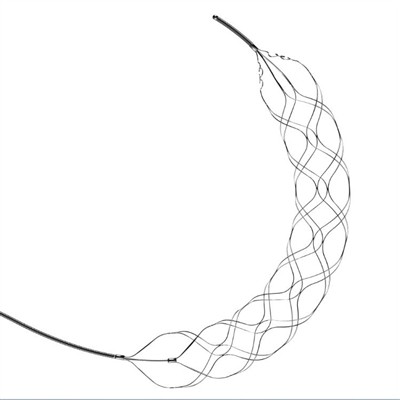

Tipi ta' apparati ta' trombektomijaIl-puplesija hija kawża ewlenija ta' diżabilità u mewt madwar id-dinja. F'dawn l-aħħar snin, l-iżvilupp ta 'apparati ta' trombectomy għat-trattament ta 'puplesija iskemika akuta irrevoluzzjona l-ġestj